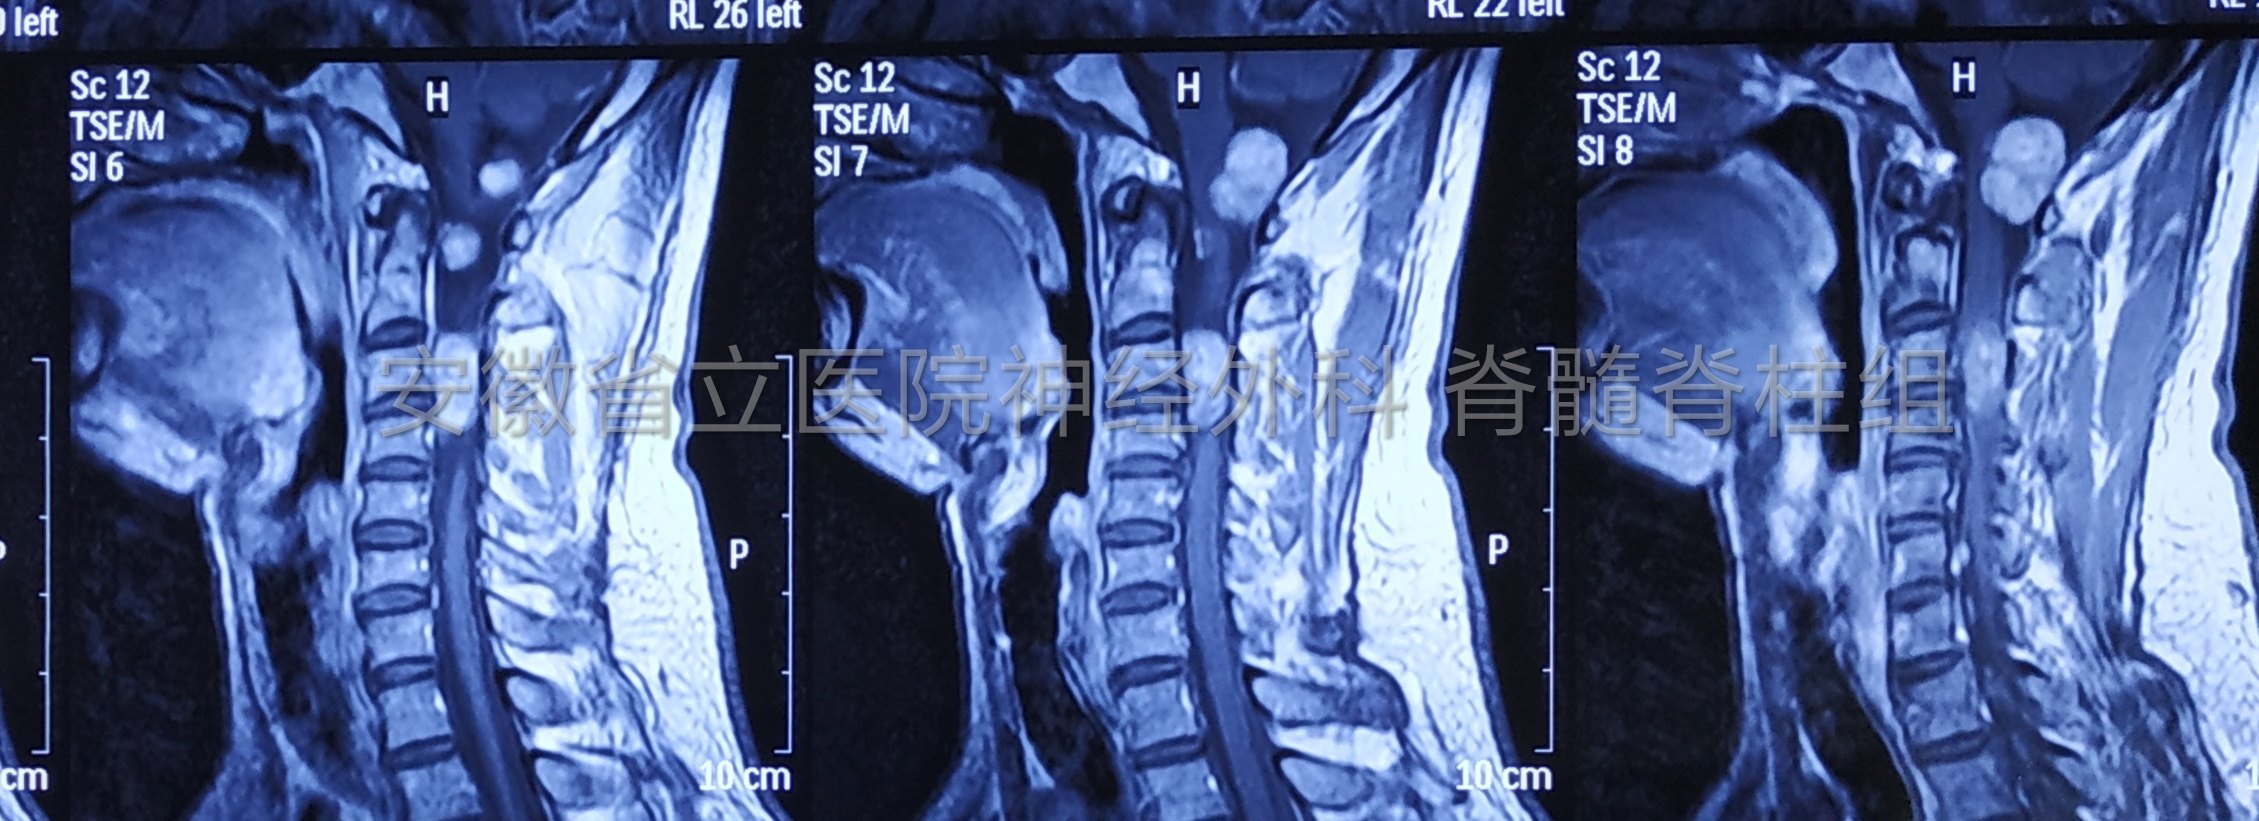

采用X射线、CT、MRI形式进行确诊,哪种方法确切率高?

(3)MRI检测

可以显示出胸膜骨膜的变化情况。因此针对X射线、CT检测所不能否显示下来的骶髂关节胸膜骨膜严恒、关节面下骨松质肿胀、渗出、脂肪集聚等确诊有着较好的优势。

在确诊初期强直性脊椎炎骶髂关节肿瘤中,分别采用X射线、CT、MRI检测方法中,MRI检测的确诊确切率最高,才能有效提升临床对脊椎炎骶髂关节肿瘤的确诊确切疗效,推动初期医治,改善病人的医治疗效,是目前初期强直性脊椎炎骶髂关节肿瘤确诊较好的方法。